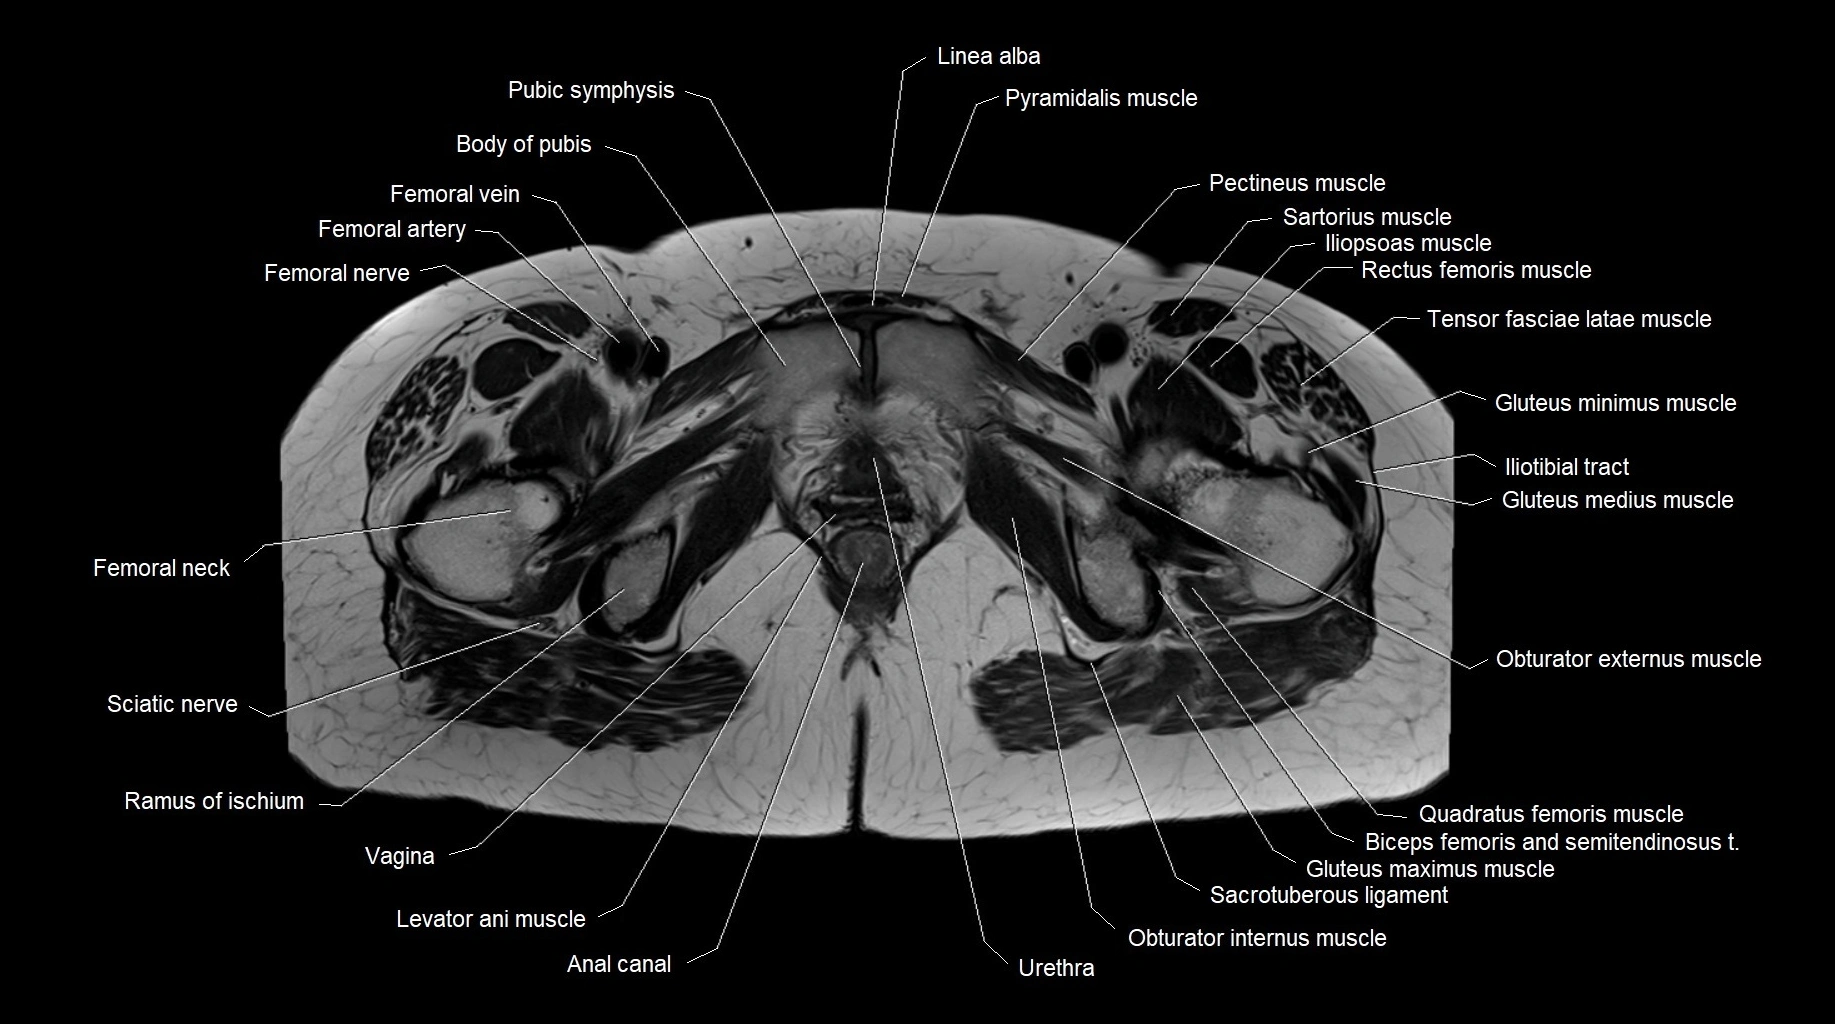

- Body of pubis

- Femoral nerve

- Femoral vein

- Iliotibial tract

- Levator ani muscle

- Linea alba

- Obturator externus muscle

- Obturator internus muscle

- Pectineus muscle

- Pyramidal muscle (pyramidalis muscle)

- Quadratus femoris muscle

- Ramus of ischium

- Sacrotuberous ligament

- Sartorius muscle

- Sciatic nerve

- Vagina